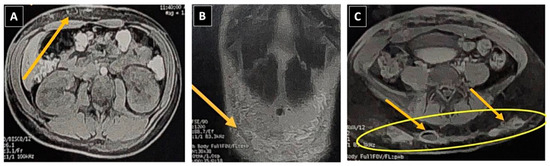

A guided puncture in the hypogastric region using ultrasound yielded purulent bloody fluid for microbiological analysis. She was then transferred back to the Infectious Diseases Service at HGR, maintaining a combined antibiotic regimen of Meropenem and Teicoplanin, with the addition of Amikacin. Upon admission, Nuclear Magnetic Resonance Imaging (MRI) of the pelvic and bilateral gluteal regions displayed postsurgical alterations in the subcutaneous tissue of the anterior abdominal wall in the hypogastrium and gluteal regions (Figure 2).

Figure 2. Magnetic Resonance Imaging (MRI) of the pelvic region. (A,B) Large collection in the hypogastrium measuring 12.3 × 2.0 cm, indicated by yellow arrows. (C) Abscesses in the gluteal regions, sizing at 3.5 × 2.0 cm on the right side and 4.2 × 2.4 cm on the left side, accompanied by a slight presence of free fluid within the pelvic cavity.